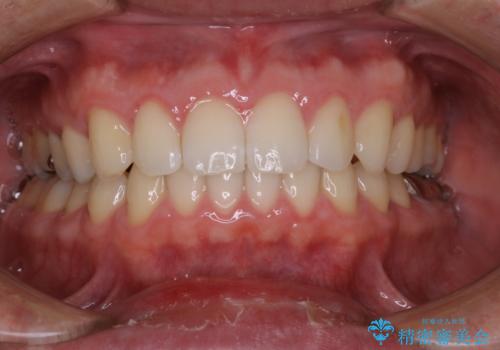

インビザラインの方法でも治せる患者様でしたが、希望によりワイヤー矯正となりました。

インビザライン治療を始めた後であっても使えないことが判明する患者様もいらっしゃいます。

当院であれば、そのような患者様の場合でも途中でワイヤー治療に切り替えて差し上げることが可能となります。